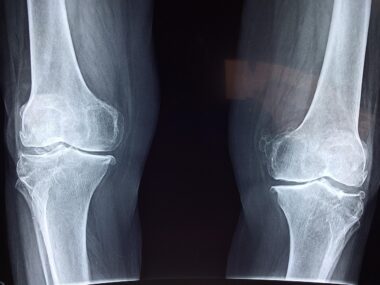

Building a strong foundation after an injury begins with understanding the nature of the injury itself. Speed skaters may face various injuries, including muscle strains, ligament sprains, or more severe conditions like fractures. Each type of injury requires a unique approach to rehabilitation and conditioning. For instance, muscle strains typically benefit from gentle stretching and progressive strengthening exercises. In contrast, ligament injuries might necessitate a more cautious regimen, focusing on stability and mobility before introducing strength training. It’s crucial to allow adequate healing time before resuming full activity levels. Engaging in low-impact exercises such as cycling or swimming can help maintain fitness levels without overwhelming the recovering body. Nutrition also plays an integral role; a well-balanced diet rich in proteins, vitamins, and minerals aids healing. Adequate hydration is equally important. Athletes can utilize various recovery modalities such as ice therapy, compression garments, and massage techniques to promote better recovery from both physical strain and inflammation. The combination of these strategies can empower athletes to return to speed skating with enhanced resilience.